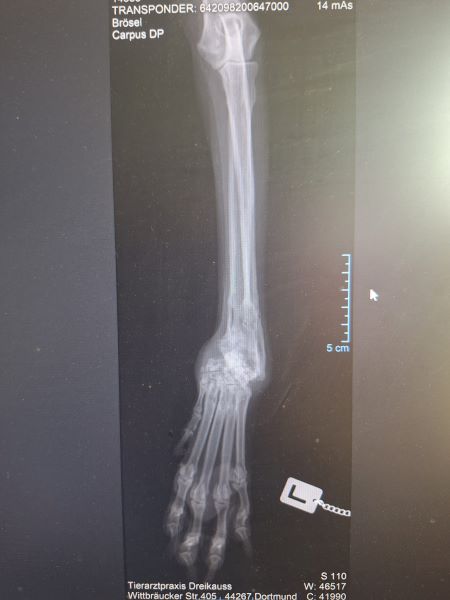

Das Röntgen seiner deformierten Vorderbeine ergab auf beiden Seiten alte, schlecht verheilt, doppelte Brüche. Man mag sich gar nicht vorstellen wie das passiert ist und wie er sich damit fortbewegt hat. Aufgrund dieser alten Brüche knickt er leider manchmal um. Generell lief er nicht so ganz rund. Durch die Brüche ist auch eine Arthrose entstanden und die Sehnen und Bänder sind nicht mehr so stabil wie sie sein sollten. Inzwischen bekommt er Schmerzmittel, welches gut angeschlagen hat. Das muss er auch dauerhaft bekommen. Wir hoffen sehr, dass dieses Mittel ihm ganz lange hilft und wir nicht auf die Suche nach einem neuen Mittel gehen müssen.